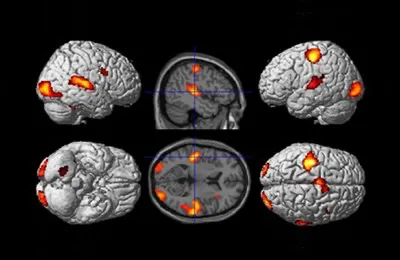

Die Hirnaktivität lässt sich farbig darstellen, wenn man das Hirn mittels Magnetresonanz-Tomografie durchleuchtet. Abb.: Benjamin StraubeSinneswahrnehmungen

kosten unser Hirn weniger Energie, wenn wir die Vorkommnisse, die wir wahrnehmen, selbst hervorrufen. Das zeigt eine Studie von Wissenschaftlerinnen

Die unterschiedlichen Aufgabenstellungen wirkten sich auf die Hirntätigkeit aus: Lösten die Beteiligten die Signale selbst aus, so sank die Sauerstoffkonzentration

des Blutes in Hirnregionen, die Zentren zur Verarbeitung visueller und akustischer Reize umfassen. „Offenbar muss das Gehirn weniger arbeiten, wenn

wir das Auftreten eines Tons oder Punkts auf dem Bildschirm vorhersagen können“, konstatiert Straube. „Diese Vorhersage-Mechanismen sind wahrscheinlich

im linken Kleinhirn lokalisiert.“